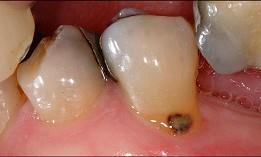

问题 导致老年人龋病发病率升高的原因是 ( )

选项 A.唾液分泌量减少 B.致龋菌的种类改变 C.牙脆性增加 D.牙根外露,根面龋发病率升高 E.食糖量增加

答案 D